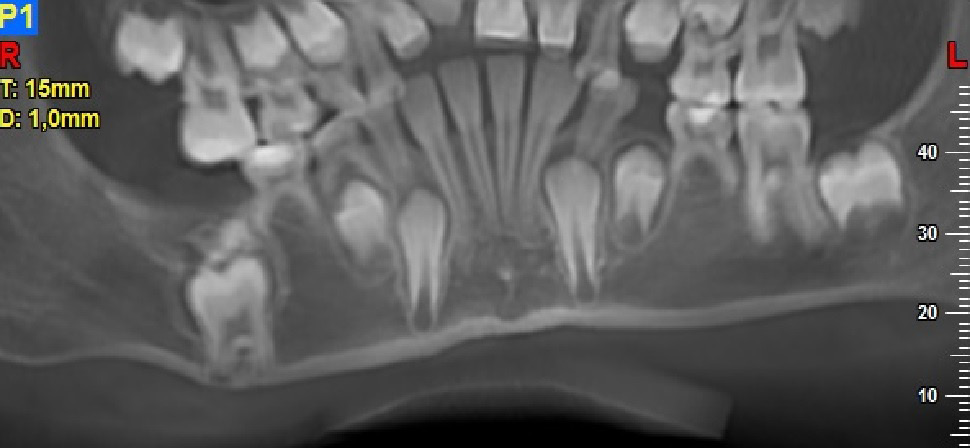

A total of 20 patients (13 (65%) boys and 7 (35%) girls), aged between 2.8 and 17.6 years (mean age: 8.96 ±4.20 years), were included in the study. The study involved general and local history-taking concerning chronic comorbidities and the medications received, dental history (the reason for the visit, presenting complaints), and extraoral (facial symmetry and lymph nodes) and intraoral (the number and type of erupted teeth, the assessment of the shape and consistency of the alveolar process) clinical examination. All patients underwent radiological and histopathological examination. Depending on the indications, tooth X-rays, panoramic radiography, CBCT and/or CT were performed. Radiological imaging was used to assess the location and type of odontoma, the presence of impacted or retained teeth, gaps, and tooth displacement. While OCp were found in X-ray images as high-density radiopacities arranged as numerous small deformed denticles (odontoids) surrounded by a band of radiolucency with an osteosclerotic border, OC were characterized by irregular radiopacities with a radiolucent edge and an osteosclerotic rim. The treatment of choice for all patients was the enucleation of the tumor with the capsule surrounding it.

The patients had the following examination performed: tooth X-ray (11 (55%)); panoramic radiography (11 (55%)); CBCT (12 (60%)); or CT (1 (5%)). X-ray images revealed 18 OCp (of which 2 were described as erupted) and 2 OC.

Radiographically, OC is a highly dense radiopacity of irregular shape, surrounded by a band of radiolucency with a sclerotic rim,6, 19 and OCp is a dense radiopacity arranged as numerous small deformed denticles (odontoids) surrounded by a band of radiolucency and a sclerotic rim.6 Similar radiological pictures were obtained for our patients. Histopathological examination should be conducted to confirm the clinical and radiological diagnosis. On microscopic examination, OCp is described as fragments of the dental pulp, dentin, enamel matrix, epithelium, and connective tissue, or as fragments of a tooth with preserved histological structure, with fragments of fibrovascular tissue. On the other hand, OC is described in histopathological findings as fragments of dentin and connective bone tissue. The histopathological picture of OC is very similar to that of an ameloblastic fibro-odontoma (AFO).20, 21 And this was the microscopic picture obtained for the lesions removed in our patients.

Recently, there has been improvement in X-ray diagnostic imaging methods, especially with regard to CBCT, which certainly facilitates arriving at diagnosis as early as at the stage of radiological examination. Jayam et al. describe a case of an 11-year-old girl with a radiological picture (panoramic radiography, a tooth X-ray and a maxillary occlusal radiograph) description of impacted tooth 11 with an additional cusp and an extensive dentigerous cyst.2 In the course of marsupialization, the dentigerous cyst was found to have no contact with tooth 11, while it contacted the adjacent additional cusp. On histopathological examination, OCp was diagnosed with a cyst. According to some authors, X-ray images – panoramic radiographs and targeted dental X-rays – may not accurately reveal the pattern of the lesion, which is why cross-sectional CBCT is recommended in the case of doubts or for more accurately determining the location.2 In the case of 2 of our patients, it was not until a CBCT was performed that the adequate diagnosis was reached, and it was later confirmed during the procedure and histopathological examination. The first patient was a 9-year-old girl referred to an orthodontist in our clinic due to impacted tooth 21 for the exposure of the tooth and the application of a bracket to the crown of tooth 21. The patient had with her a current panoramic radiograph with visible impacted tooth 21, showing a small non-distinctive radiopacity in the tooth crown, which could be consistent with an additional cusp. An X-ray of tooth 21 was performed at our clinic, revealing a non-distinctive area of radiopacity next to the crown of tooth 21 (Figure 7). The patient was referred for cross-sectional CBCT. After verification, OCp was diagnosed and removed with its capsule, and an orthodontic bracket was attached to tooth 21 in local anesthesia (Figure 8). Histopathological examination confirmed the preliminary diagnosis of OCp. The other patient was a 5-year-old girl who was admitted to our clinic with a missing deciduous tooth 65. The patient had a current panoramic radiograph with her, revealing an impacted tooth (most probably tooth 65) with a non-distinctive area of radiopacity (Figure 9). Cross-sectional CBCT was recommended. In the X-ray image, the preliminary diagnosis suggested OCp with the impacted deciduous tooth 65 above it and the tooth bud of permanent tooth 25 on the palatal side (Figure 10). The procedure involved the resection of the impacted deciduous tooth 65 and the enucleation of the odontoma with its capsule; the tooth bud of tooth 25 was left. Due to the child’s age and her poor cooperation, the procedure was carried out in general anesthesia. Histopathological findings revealed OCp.